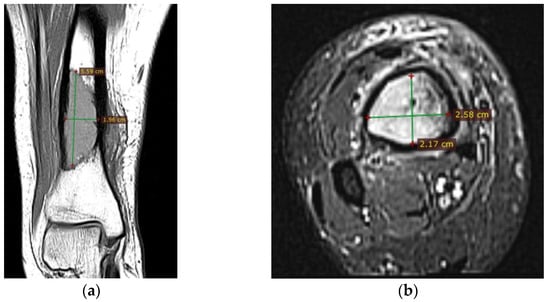

Corroborating the clinical examination with the patient’s history, we had decided to investigate again radiological and imaging (CT, MRI). Radiological and CT examination showed a slight increase in the size of the tumor formation, confirmed by MRI images (Figure 3), at this time the dimensions being 5.5/1.95/2.2 cm. Radiological and CT features were similar, osteolytic lesion with thinning and disruption of the bone cortex, associating periosteal reaction (Figure 4). However, this time, the CT images show the extraosseous expansion of the tumor formation, through the bone window created by the initial biopsy (Figure 5).

MRI examination clearly shows the extraosseous, subcutaneous expansion of the tumor formation through the cortical bone defect. This extraosseous expansion is in the continuity of the intraosseous tumor tissue, with the same imaging characteristics, having dimensions of 2.92/3.2/1.5 cm and well-defined edges, encapsulated (Figure 6).

Figure 3. (a) MRI T1 coronal section, hyposignal lesion; (b) MRI T1 fat sat, axial section.